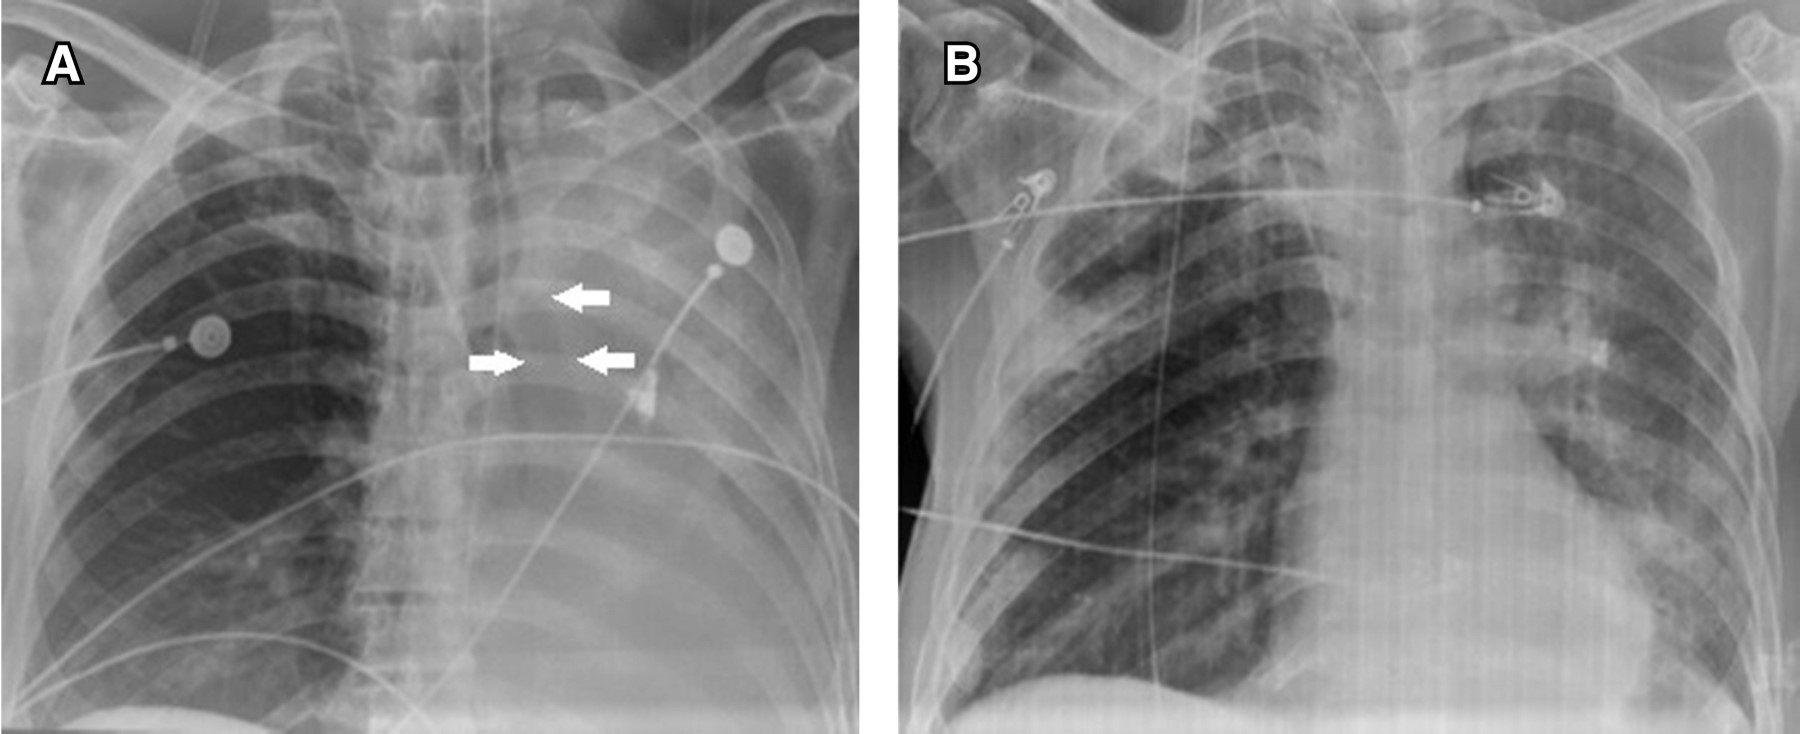

Logramos obtener información de ocho pacientes que cursaron con ALA durante los últimos dos años y que ameritaron tratamiento mediante broncoscopia (Figura 1). En todos los casos no hubo evidencia de broncograma aéreo, lo que indicó un proceso obstructivo proximal a nivel de alguno de los bronquios principales y, consecutivamente, en todos se documentaron grandes tapones obstructivos causados por la presencia de moco espeso y adherente en alguno de los bronquios principales: siete en el bronquio principal izquierdo y sólo uno en el bronquio principal derecho. Siete de los ocho procedimientos realizados se consideraron exitosos. No obstante, el pronóstico de vida y complicaciones dependió más de la enfermedad de base que de la ALA en sí y hubo tres fallecimientos, dos de ellos por traumatismo severo (pacientes uno y ocho) y otro por edema cerebral (paciente siete). La mejoría clínica y radiológica se observó inmediatamente posterior al procedimiento en seis pacientes y en otro fue parcial, pero al siguiente día hubo una completa resolución de la atelectasia lobar (paciente seis). El paciente ocho presentó como complicación un neumotórax bilateral y enfisema subcutáneo que ameritaron drenaje pleural con tubo. Dicha complicación se atribuyó a que el broncoscopio fue introducido por un orificio de una cánula de traqueostomía muy estrecho, lo que pudo haber impedido la liberación del exceso de presión aplicada durante las insuflaciones manuales con la bolsa de Ambu.

El mayor beneficio y ventaja de un abordaje broncoscópico en pacientes con un colapso pulmonar completo, o casi-completo, es la posibilidad de inspeccionar directamente las vías respiratorias y la opción de obtener muestras de líquidos o tejidos para un diagnóstico definitivo, reservando el manejo conservador para pacientes con atelectasias segmentarias o subsegmentarias10 (Figura 2). La broncoscopia para el tratamiento de la ALA es beneficiosa en la mayoría de los pacientes de la UCI al mejorar el intercambio de gases y las propiedades mecánicas del sistema respiratorio, con efectos positivos que duran hasta 24 horas.11

La insuflación selectiva es reservada para aquellos casos de ALA refractarios a tratamientos convencionales, por lo regular ya con una duración de más de cinco días. Todos nuestros casos correspondieron a ALA de más de ese periodo de tiempo y el pulmón izquierdo fue el más afectado, lo cual es explicable por la diferencia anatómica entre el bronquio principal derecho y el izquierdo, cuya posición más horizontal lo hace de difícil acceso para los catéteres de aspiración de secreciones. La mejoría clínica y radiológica fue observada al poco tiempo de realizada la maniobra de insuflación en la mayoría de nuestros pacientes y sólo en los casos cinco, seis y siete, observamos la mejoría en una forma más gradual y, probablemente, como lo mencionan Susini y colaboradores,18 después de una reexpansión parcial inicial puede observarse una mejoría espontánea adicional 24 horas más tarde, debido a que la reexpansión incompleta en sí puede promover un reclutamiento alveolar adicional en las áreas menos distensibles. En los tres casos mencionados, el lóbulo inferior izquierdo fue más difícil de expandir, tal vez porque durante la posición totalmente supina, el peso del corazón y el mediastino estrecha y pellizca los bronquios del lóbulo inferior izquierdo.1 Nuestra sugerencia sería realizar un mayor número de insuflaciones en dicho lóbulo.